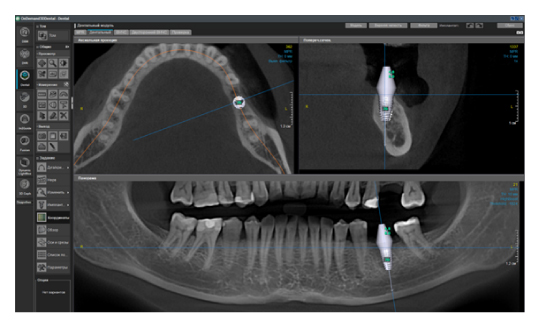

4. Универсальность программы-просмотровщика

Ещё одна актуальная проблема в современной стоматологии — это огромное количество разных программ просмотровщиков конусно-лучевой компьютерной томографии. Каждый производитель этого ПО старается сделать что-то уникальное, и для конечного доктора это порой усложняет диагностику. Вы привыкли работать в одной программе, а тут уже пришел пациент с КЛКТ исследованием в совершенно незнакомом софте. У меня даже существует отдельный курс по разбору разных программ, чтобы врач всегда мог сориентироваться и провести консультацию. Но если вы решили купить собственный дентальный томограф, то здесь совет брать программу, которая технически удовлетворит все ваши запросы. Стоит помнить о том, что если вы будете проводить исследования не только для нужд своей клиники, но и сторонним, то эта программа не должна быть обрезанной по функционалу, являться простой, русифицированной, а также знакомой и понятной многим. От себя хочу добавить, что советую обращать внимание на возможность использования различных фильтров резкости изображения, изменения толщины среза, возможность построения произвольных кросс-секций на панорамном реформате, а также большой базы имплантатов (рис. 5), и чтобы всё это было доступно не только в лицензии, но и во viewer (просмотровщике, который получает конечный врач).

Рис. 5. Пример программы OnDemand3D. Панорамный реформат с повышенным фильтром резкости, произвольной кросс-секцией, установленным виртуальным имплантатом.